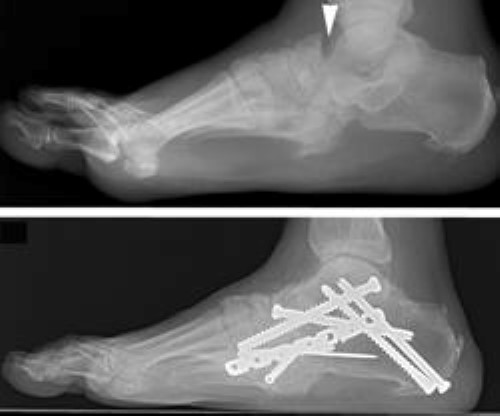

x-ray of surgery for charcot of hindfoot

(Top) In this X-ray taken from the side, the patient has unstable Charcot of the back of the foot (hindfoot). The dislocation of the joints is seen where the two bones in the back of the foot do not line up (arrowhead). (Bottom) A complex realignment and fusion was performed to prevent the patient from developing a prominence and ulceration.